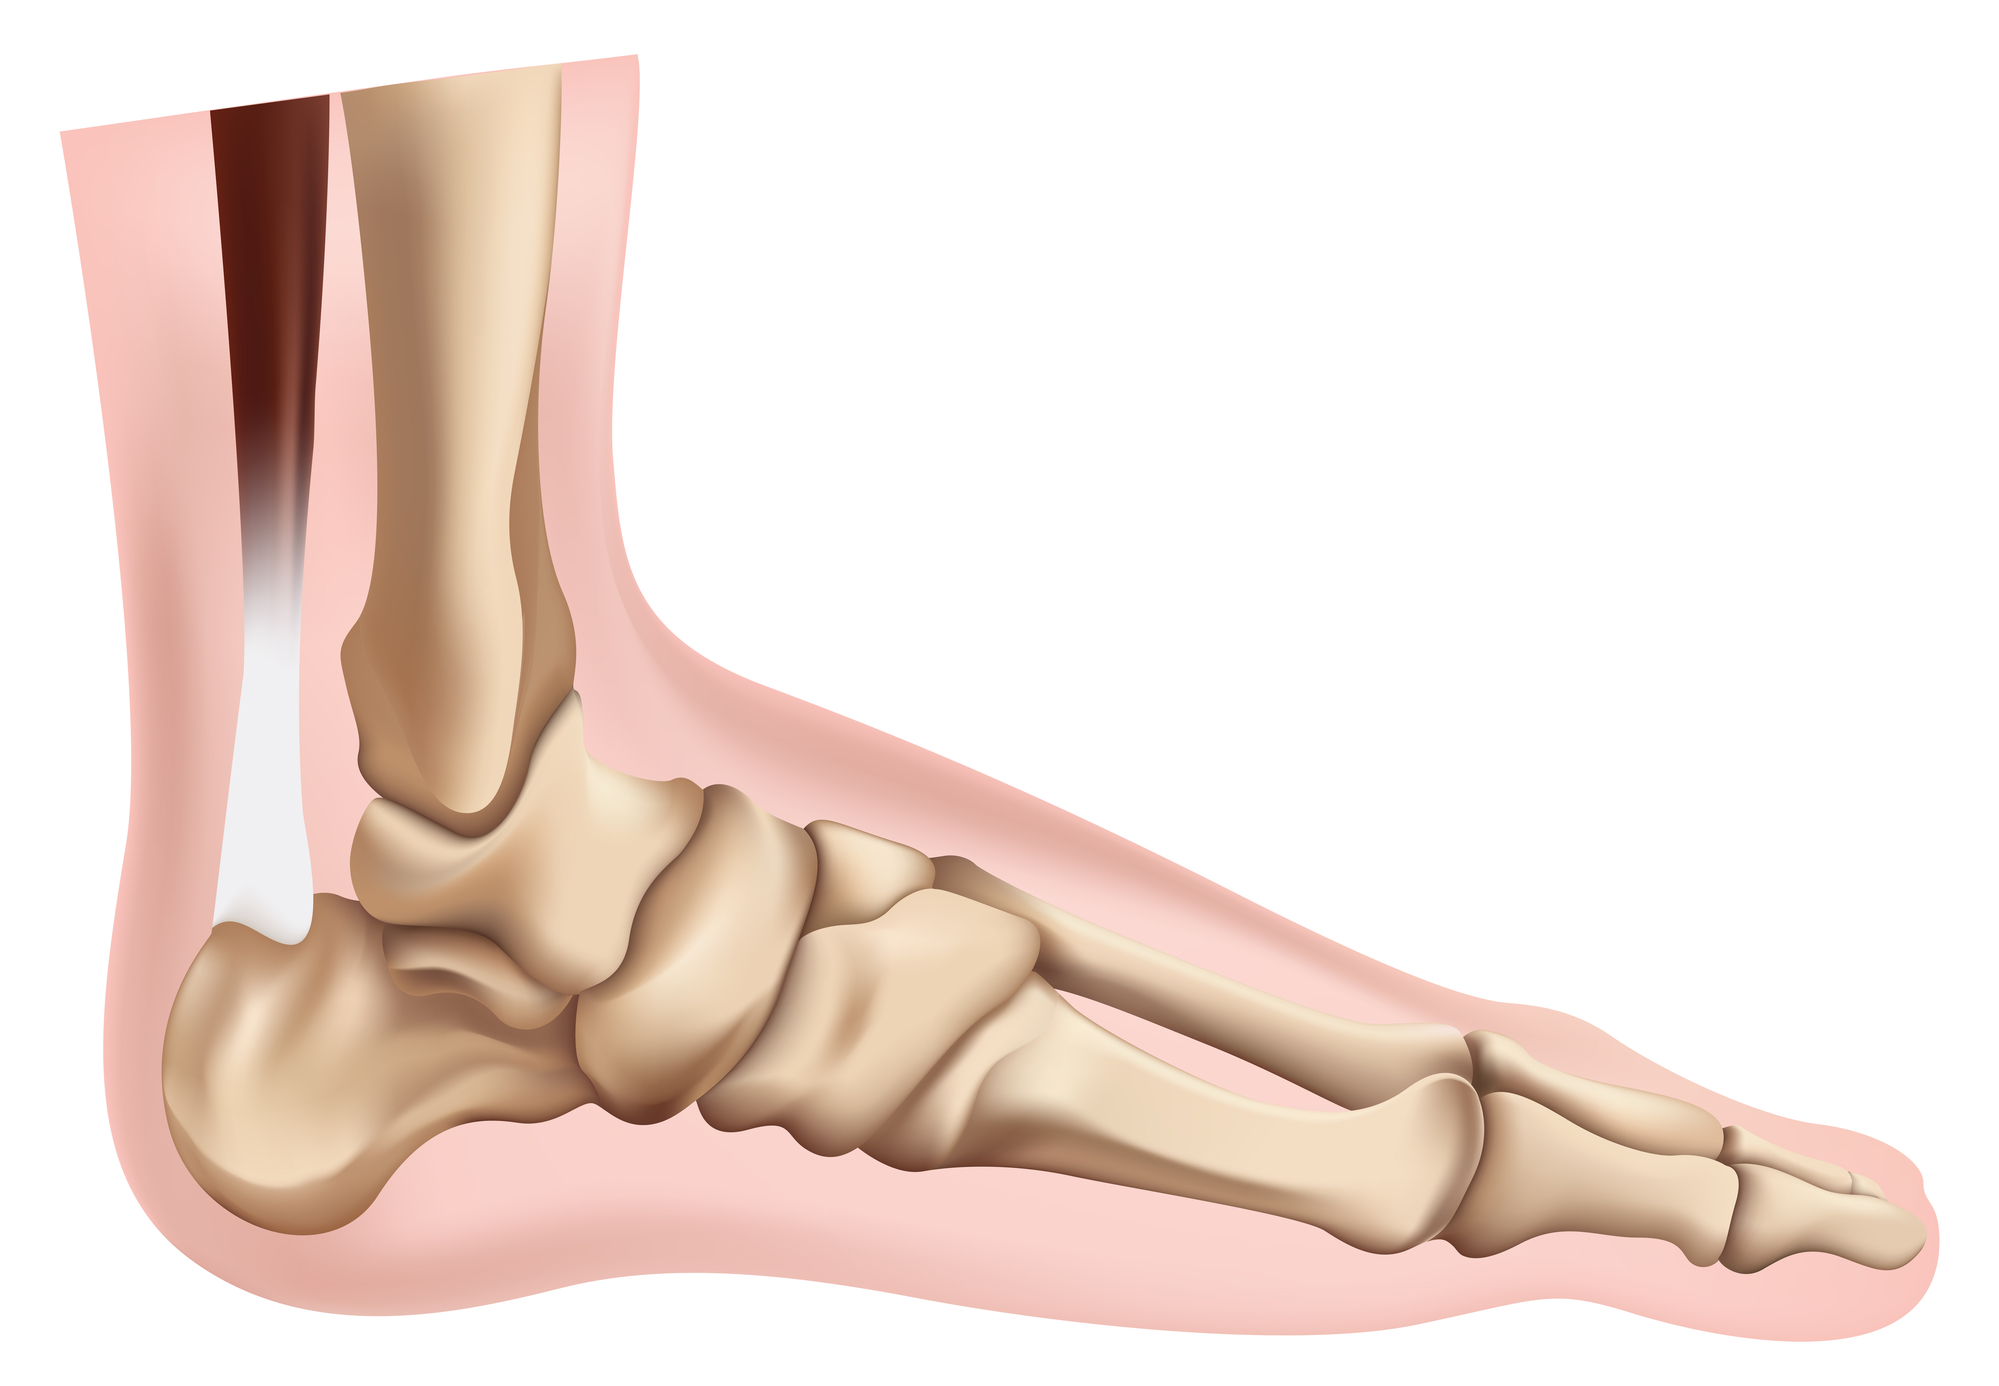

Arthritis is the inflammation of one or more of your joints and is common in the ankle joint. The major types of arthritis that affect the ankle are osteoarthritis, rheumatoid arthritis, and post-traumatic arthritis. All types can cause pain and stiffness in the ankle joint and make it difficult to walk and participate in activities you enjoy. Three bones make up the ankle joint, primarily enabling up and down movement:

- Tibia (the shin bone)

- Fibula (the thinner bone running next to the shin bone)

- Talus (the foot bone that sits above the heel bone)

The ends of the bones are covered with articular cartilage that allows pain-free motion. Ankle arthritis involves the loss of cartilage in the ankle joint. Over time, bone spurs, pain, and deformity may develop. There is no cure for arthritis, but there are a number of conservative treatments that may help relieve your ankle pain:

During total ankle replacement, arthroplasty, your DOC surgeon removes the damaged cartilage and bone, resurfaces the ends of the tibia and talus, and positions the new metal and plastic implant to replicate the ankle joint and its function. In most cases, total ankle replacement surgery relieves the pain of arthritis and enables you to return to daily activities. Full recovery may take four to nine months, depending on the severity of your condition before surgery and the complexity of your procedure. Your DOC surgeon will recommend DOC physical therapy to help you regain strength in your ankle and restore range of motion.